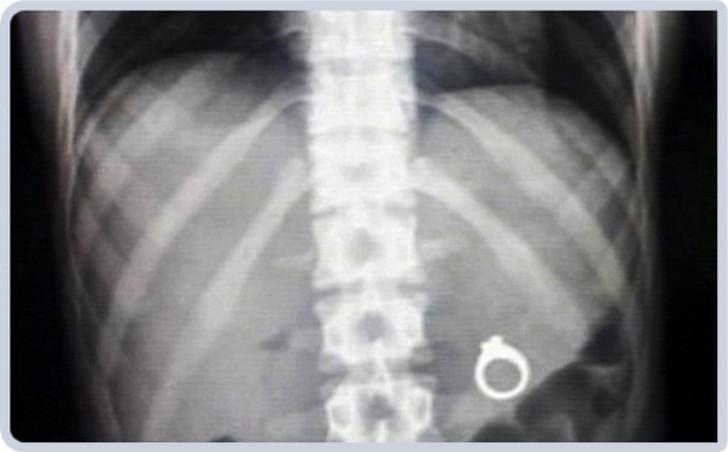

3. Обручальное кольцо.